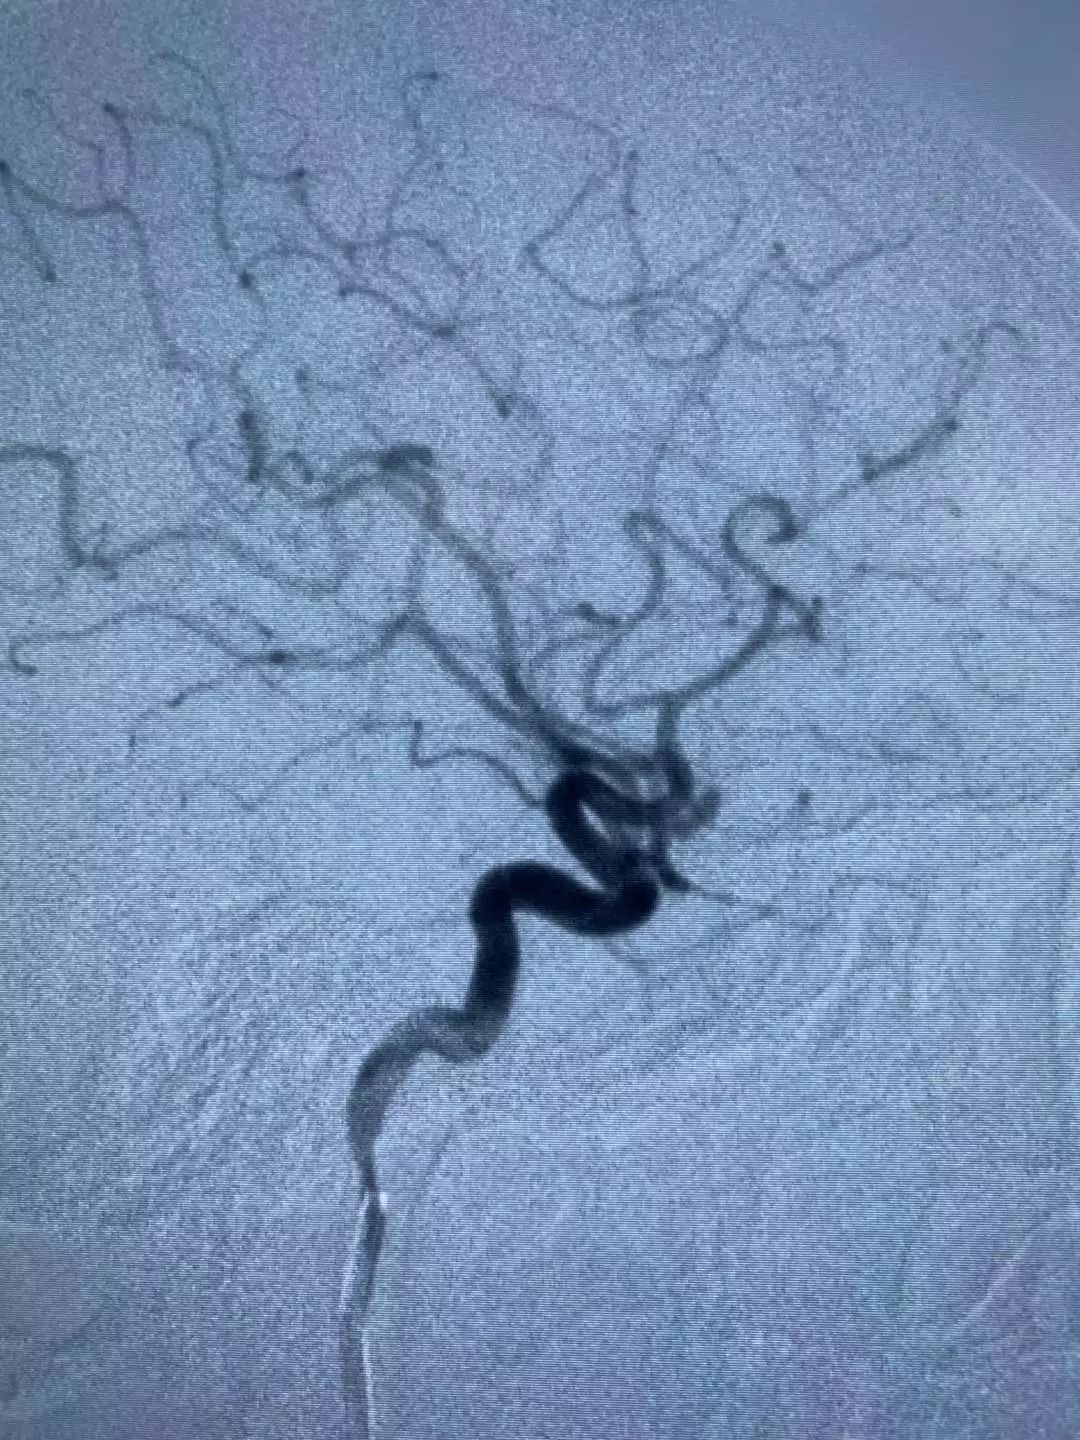

△ 脑血管造影检查图像

通过脑血管造影检查显示,患者脑出血原因是动脉瘤破裂,患者左侧大脑中动脉分叉部位长了一个动脉瘤,动脉瘤呈串珠状,长8毫米,宽3毫米。